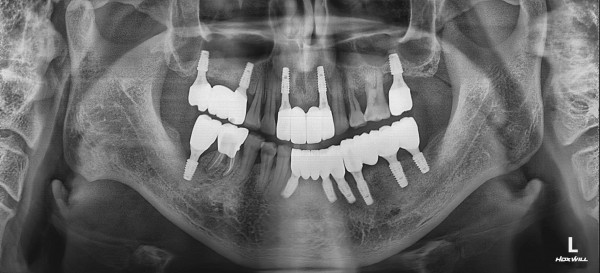

CASE 01 최고관리자 0건 25-01-06 11:57 본문 상악동거상술 임플란트 목록 이전글CASE 01 25.01.06 다음글CASE 02 25.01.06 댓글목록 0 댓글목록 등록된 댓글이 없습니다.